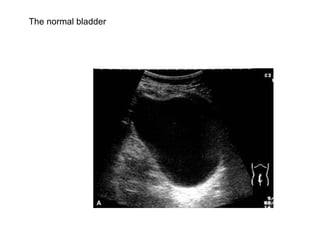

The normal bladder

Normal bladder